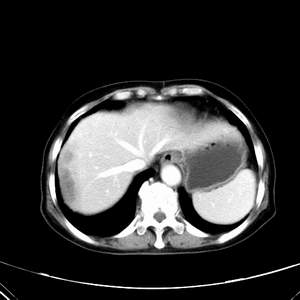

患者,女性,77岁,右上腹胀痛月余。afp正常。ca125升高。即往无肝炎病史。

肝右叶病灶是胆管细胞癌吗?门静脉右支癌栓形成?右侧肾上腺有问题吗?

快进快出符合肝癌表现

最后5幅图片是延时7分钟的。门静脉右前支内有充缺吗?如有,肝血管瘤不好解释。

病灶渐进性向心性强化,延时病灶中心见条片状高密度影,局部见肝包膜回缩征,结合病人无肝炎病史,考虑肝右叶胆管细胞癌,门脉右支癌栓形成。